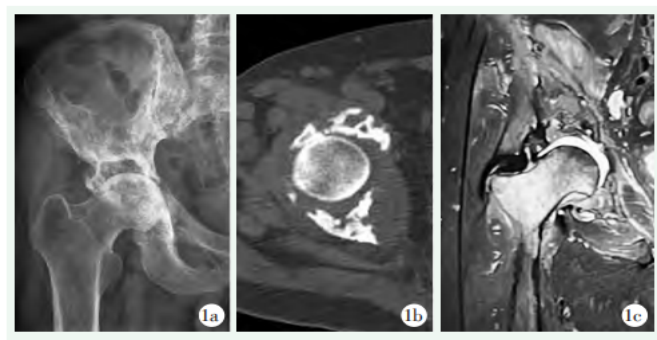

X线片示:右侧髋臼骨质破坏及双侧骶髂关节破坏,右侧髂骨及骶骨骨质密度不均匀(图1a)。

CT示:骨盆诸骨骨质破坏,局部骨质呈虫蚀样改变(图1b)。

MRI示:右侧股骨头、颈部边缘毛糙,囊变,双侧髋关节退行性改变,右侧为著(图1c)。